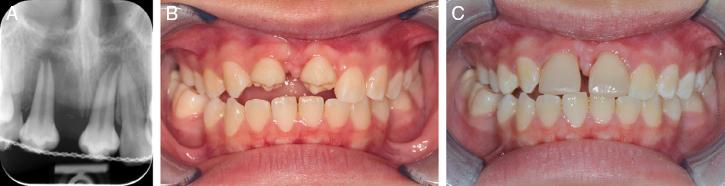

An 11-year-old healthy girl visited the clinic with the chief complaints of an uneven smile, after suffering dental trauma to her upper incisors (Figure 7A-H). The upper right lateral incisor (#12) and upper left central incisor (#21) had been subluxated, while the upper right central incisor (#11) suffered a complicated crown fracture which extended subgingivally. Teeth #12 and #21 were root canal treated and displayed radiographic evidence of progressive replacement resorption, while #11 was decoronated 2 mm below the cemento-enamel junction for alveolar bone preservation (Figure 8A-D). She was referred by the paediatric dentist for multidisciplinary management and extractions of #12 and #21, after infra-occlusion of these teeth was observed.

(A) Pretreatment panoramic radiograph. (B) Periapical radiograph showing decoronated #11 and crown attached; Resorption on the apical surfaces of #12 and #21. (C) Lateral cephalogram. (D) CBCT section showing developing tooth #35 with ⅔ root length and (E) Developing tooth #45 with ¾ root length.

An initial examination revealed a Class II malocclusion and a straight profile with 9 mm of incisal display on smiling. She was in the permanent dentition with a decoronated upper right central incisor (#11) and its crown bonded to the adjacent tooth for aesthetics. She had a unilateral crossbite without displacement on the right side extending from #12 to #16. Her upper dental midline had shifted to the left of the facial midline by 2 mm, and her lower second permanent molars were impacted mesio-angularly. The overjet was 6 mm and the molar relationships were a ½ unit Class II on the right and a ¼ Class III on the left (Table II).